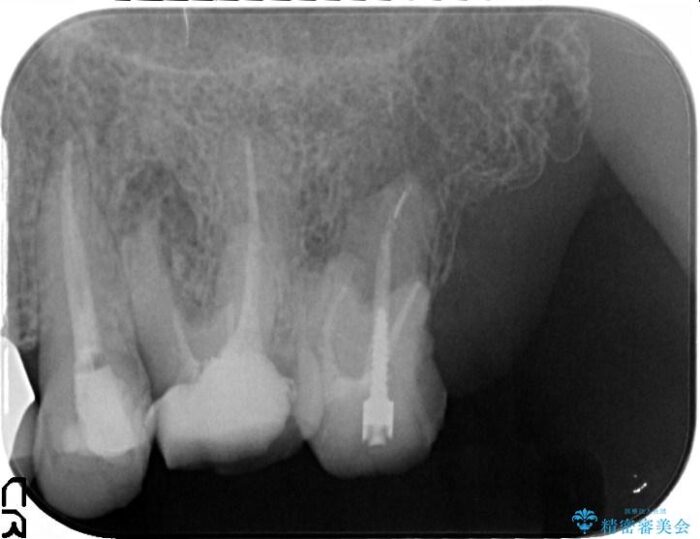

他院での治療の途中で通院をやめてしまい、当院で治療の続きを希望された患者様です。

クラウンが装着されておらず、つぎはぎだらけの処置歯を、精度の高いセラミッククラウンを用いて歯ブラシのしやすい環境整備を行っていきます。